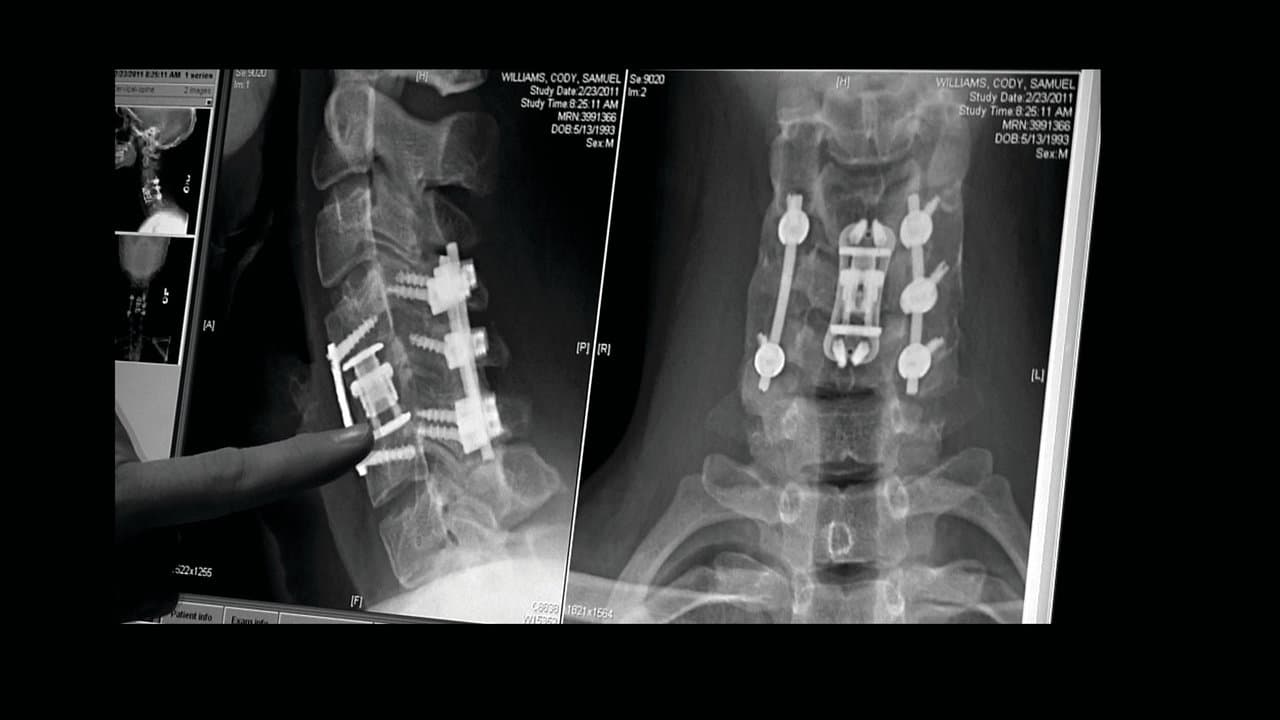

The compelling, heart-wrenching story of high school football star Chris Carnales, whose life changed when he became paralyzed after breaking his neck in a football game. Chris soon learned of others who suffered similar injuries and, with the help of his father, overcame tremendous pain to start an organization with one goal in mind: get immediate help to other victims and their families. He called it Gridiron Heroes.